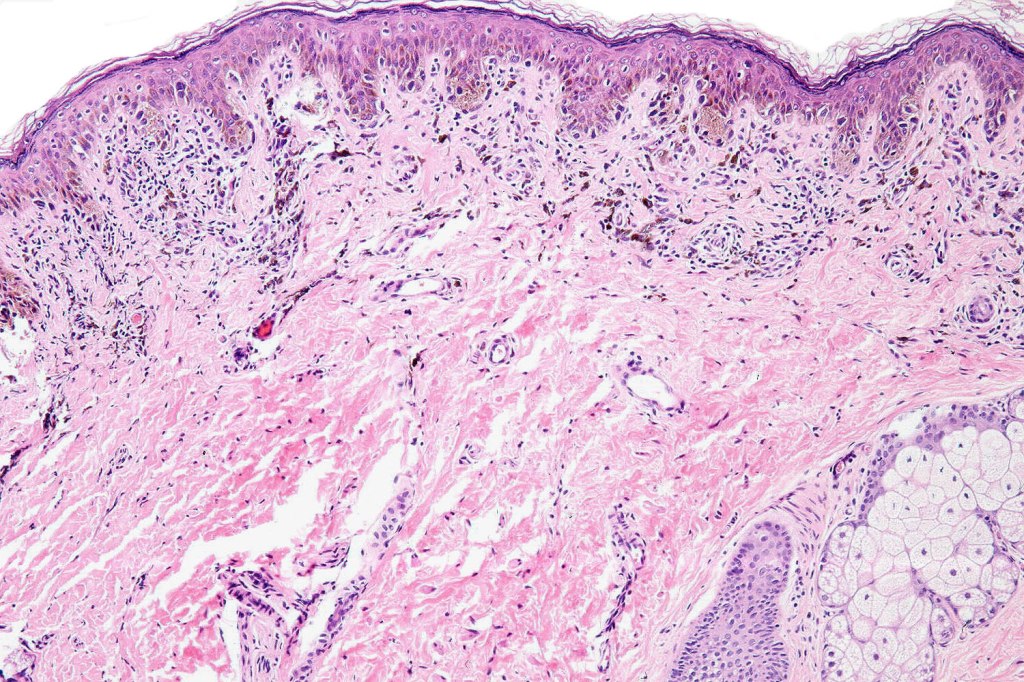

•Diffuse infiltrate of nevus cells often extending deeply into the dermis or beyond, single filing is often present at base & may involve the septa of the subcutaneous fat

•Involvement of appendages & arrector pili muscles

•Neurotization, neurofibroma-like lesions & neurocristic hamartoma

This melanoma arose in a small congenital nevus of the scalp. It metastasized widely. Varying features in different fields.